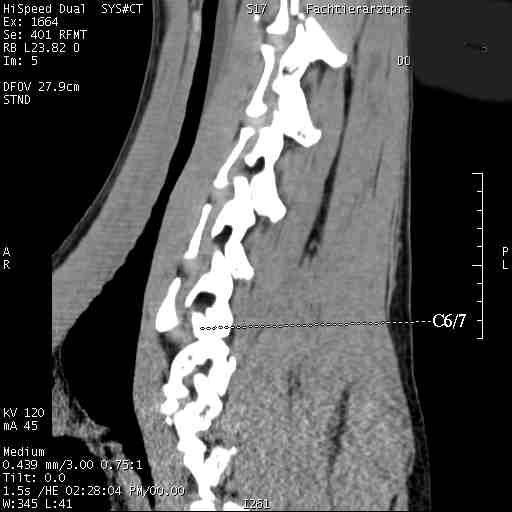

Im folgenden Beispiel sieht man computertomografische Bilder der Halswirbelsäule einer Dogge mit folgender Diagnose: Knöcherne Stensoe C3/4 [= 3./4. Halswirbel], sanduhrförmige Kompression des Myelons auf der Höhe C3/4, Bandscheibenvofall C6/7 [= 6./7. Halswirbel], Myelon mit seitlicher Abweichung nach links : Im Ergebnis eine Halswirbelstenose an den beiden Stellen mit Kompression des Myelons, die zu den Lähmungserscheinungen führt.